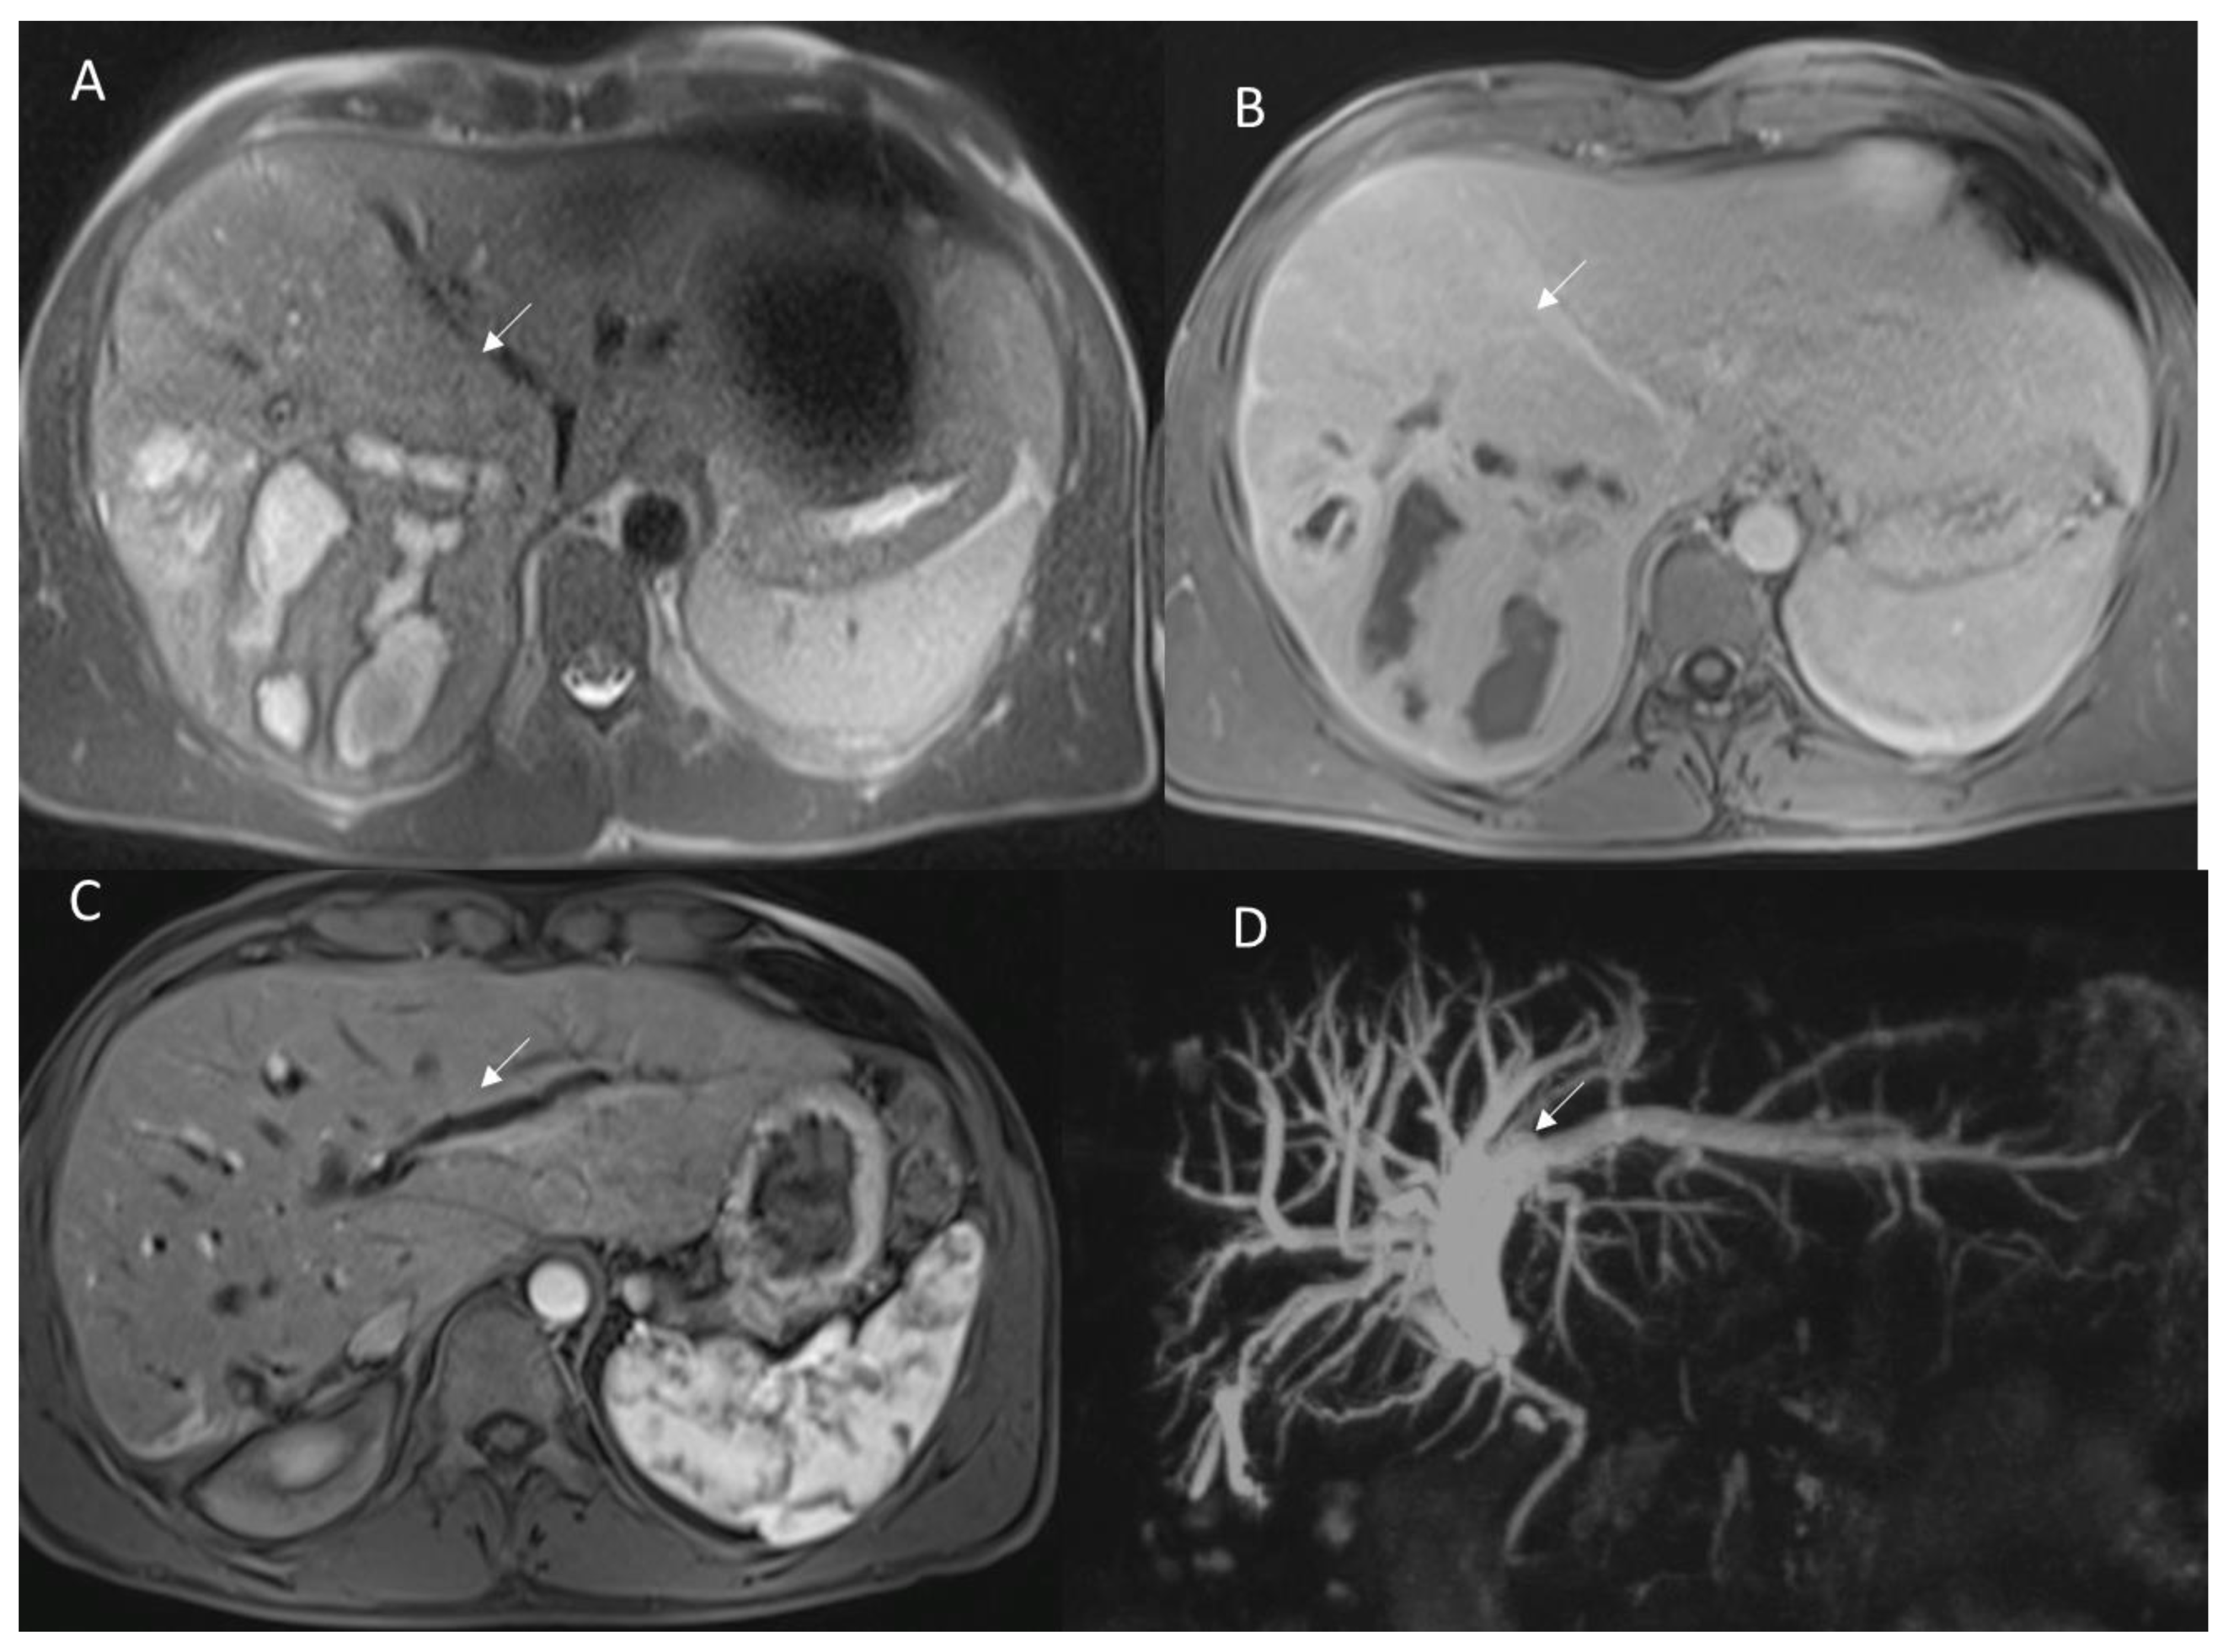

3.2. Late Postoperative Complications

3.2.1. Disease Recurrence

3.2.2. Late Strictures and Ischemic Cholangitis

- Hoeffel, C.; Azizi, L.; Lewin, M.; Laurent, V.; Aubé, C.; Arrivé, L.; Tubiana, J.M. Normal and pathologic features of the postoperative biliary tract at 3D MR cholangiopancreatography and MR imaging. Radiographics 2006, 26, 1603–1620. [Google Scholar] [CrossRef] [PubMed]

- Yamashita, Y.; Hamatsu, T.; Rikimaru, T.; Tanaka, S.; Shirabe, K.; Shimada, M.; Sugimachi, K. Bile leakage after hepatic resection. Ann. Surg. 2001, 233, 45–50. [Google Scholar] [CrossRef] [PubMed]

- Nagano, Y.; Togo, S.; Tanaka, K.; Masui, H.; Endo, I.; Sekido, H.; Nagahori, K.; Shimada, H. Risk factors and management of bile leakage after hepatic resection. World J. Surg. 2003, 27, 695–698. [Google Scholar] [CrossRef] [PubMed]

- Park, M.S.; Kim, K.W.; Yu, J.S.; Kim, M.J.; Kim, K.W.; Lim, J.S.; Cho, E.S.; Yoon, D.S.; Kim, T.K.; Lee, S.I.; et al. Early biliary complications of laparoscopic cholecystectomy: Evaluation on T2-weighted MR cholangiography in conjunction with mangafodipir trisodium-enhanced 3D T1-weighted MR cholangiography. AJR Am. J. Roentgenol. 2004, 183, 1559–1566. [Google Scholar] [CrossRef] [PubMed]

- Alegre Castellanos, A.; Molina Granados, J.F.; Escribano Fernandez, J.; Gallardo Muñoz, I.; Triviño Tarradas Fde, A. Early phase detection of bile leak after hepatobiliary surgery: Value of Gd-EOB-DTPA-enhanced MR cholangiography. Abdom. Imaging 2012, 37, 795–802. [Google Scholar] [CrossRef] [PubMed]

- Melamud, K.; LeBedis, C.A.; Anderson, S.W.; Soto, J.A. Biliary imaging: Multimodality approach to imaging of biliary injuries and their complications. Radiographics 2014, 34, 613–623. [Google Scholar] [CrossRef] [PubMed]

- Ward, J.; Sheridan, M.B.; Guthrie, J.A.; Davies, M.H.; Millson, C.E.; Lodge, J.P.; Pollard, S.G.; Prasad, K.R.; Toogood, G.J.; Robinson, P.J. Bile duct strictures after hepatobiliary surgery: Assessment with MR cholangiography. Radiology 2004, 231, 101–108. [Google Scholar] [CrossRef] [PubMed]